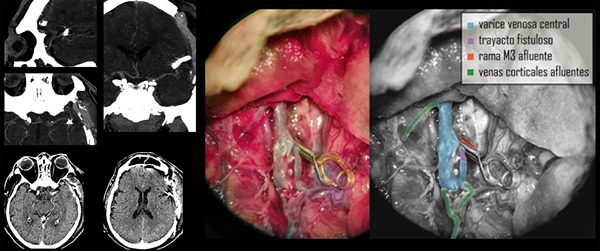

Con la premisa de actuar en forma urgente para evitar resangrado y luego de superado un evento infeccioso de origen respiratorio, se decide realizar una nueva cirugía a los 5 días de su ingreso con el objetivo de tratar la lesión vascular de alto flujo. En quirófano se pudieron constatar con precisión los datos obtenidos por imágenes de la angioarquitectura patológica. Se inició por la disección microscópica del valle silviano, exposición de los vasos comprometidos y control proximal vascular de la malformación. Se identificó un trayecto fistuloso de entre 5 y 7 mm de largo que provenía de una rama M3 que drenaba en el trayecto varicoso central. Se realizó clipado transitorio en la base de este trayecto y coagulación de 2 pequeñas aferencias fistulosas a la várice.

Luego de comprobar disminución notable del flujo y el volumen de la várice venosa, se colocó clip definitivo. La várice venosa en su tramo distal presentaba afluentes venosos de caracteres normales que provenían de la corteza, por lo cual no se realizó ningún otro gesto sobre la misma. Se realizó cierre por planos y craneoplastia con polimetil-meta-acrilato (PMMA). Se dejó un catéter subdural para control de la presión intracraneana.

En forma inmediata se tomaron medidas de control de la presión arterial para disminuir los riesgos de sangrado. Al cabo de 24 horas se reinició también la terapia antitrombótica. A las 48h de registro de presión intracraneal normal y sin cambios significativos en el examen físico (paciente sedado en ARM) se realiza imagen de control (TC y AngioTC) en la cual puede observarse ausencia de nuevas lesiones hipodensas, presencia de clip vascular en cisura silviana, permeabilidad de vasos silvianos distales al clipado, disminución significativa del volumen original de la várice venosa, desaparición del higroma contralateral, surcos y cisuras presentes en el hemisferio derecho y ligero edema regional fronto temporal izquierdo (Figura 4).

Figura 4. TC y AngioTC de control postoperatorio y fotografía quirúrgica esquematizada.